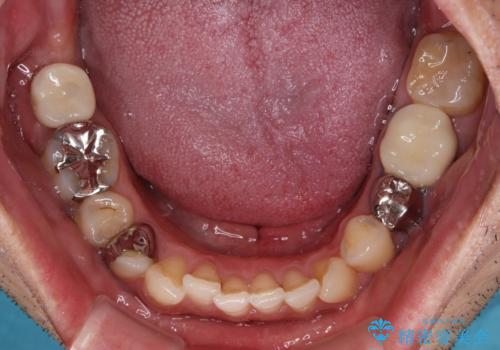

目立つ銀歯と欠けてしまった詰め物 オールセラミッククラウンでの補綴治療